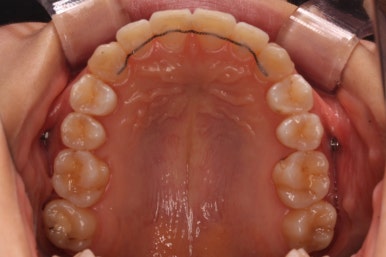

위 사진은 연산동교정치과 처음 내원하셨을 때의 입안 모습입니다. 몇 가지 모습이 관찰됩니다.

치아가 삐뚤삐뚤합니다.

위~아래 앞니가 많이 겹쳐서 아랫니가 많이 모이지 않는 "과개교합" 입니다.

앞니가 앞으로 뻐뜨러져 있습니다.